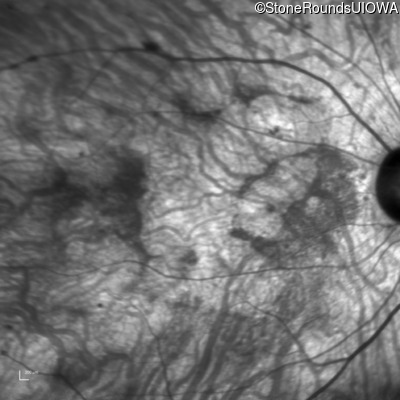

Infrared Fundus Photograph - Left - 10/225

Exemplar